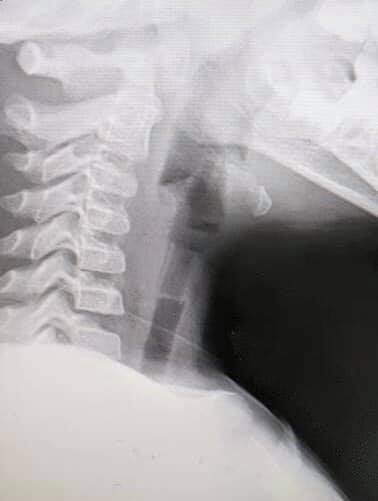

แพทย์หญิงกฤษณพร ผู้โพสต์คลิป และเป็นแพทย์ที่รักษาเด็กชาย เปิดเผยว่า วันเกิดเหตุคือวันที่ 5 มีนาคมที่ผ่านมา ได้รับตัวเด็กชายคนนี้ที่ส่งต่อมาจากจังหวัดนราธิวาส หลังเด็กชายมีอาการไออย่างรุนแรง เนื่องจากสำลักสิ่งแปลกปลอม ขณะรับตัวเข้ารักษาขณะนั้นเด็กไม่มีอาการผิดปกติ เพียงแต่หายใจแล้วมีเสียงดัง “วี้ด วี้ด” ตามคลิป และเด็กก็ไม่ได้ตื่นกลัวอะไร เมื่อเอกซเรย์พบว่าสิ่งแปลกปลอมดังกล่าว เข้าไปตกค้างบริเวณหลอดลมส่วนต้น จึงวางยาสลบ และคีบออกมาได้สำเร็จ โดยใช้เวลาในการรักษา 15-20 นาที ก่อนจะให้เด็กชายพักดูอาการที่โรงพยาบาล 1 คืน วันรุ่งขึ้น (6 มี.ค.) ก็เดินทางกลับบ้านได้

จากการตรวจสอบพบว่า เป็นนกหวีดเป่าลมที่ติดอยู่กับลูกโป่ง ขนาดความยาวประมาณ 1.5 เซนติเมตร และเส้นผ่านศูนย์กลางประมาณ 1 เซนติเมตรเท่านั้น ซึ่งแพทย์เตือนให้พ่อแม่ผู้ปกครองระมัดระวังของเล่นบางชนิดไม่เหมาะกับเด็กในวัยนี้ เพราะอาจเกิดกรณีสำลัก หากปฐมพยาบาลไม่ถูกวิธี หรือส่งรักษาไม่ทันเวลา อาจทำให้เด็กเสียชีวิตได้